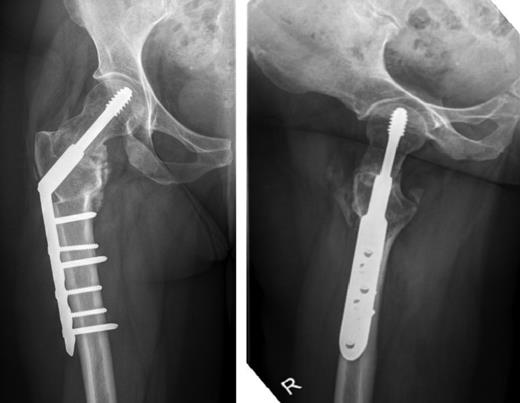

Anterior-posterior and lateral radiographs taken 6 months postoperatively demonstrating union of the fracture and osteotomy site.

Morbidity from femoral neck fractures is linked to the degree of fracture displacement and risk of AVN and non-union [2]. Other complications include disuse osteopenia, femoral neck resorption, proximal migration of the greater trochanter, difficult reduction and high failure rates of internal fixation [6]. Management options for missed femoral neck fractures, broadly speaking, are either femoral head replacement, or salvage surgery with some form of fixation. In young patients, preservation of the femoral head is preferable with joint replacement reserved as a last resort. A number of fixation methods have been used with varying success [7]. Valgus intertrochanteric osteotomy, where a lateral wedge is removed at the upper border of the lesser trochanter, allows lateral displacement of the distal fragment and valgus correction of the deformity. This has been shown to be successful in treating missed femoral neck fractures with favourable outcomes [3, 6 –8]. However, under-correction of the deformity can lead to failure of the fixation [7] and subsequent conversion to hip replacement will technically be more difficult as a secondary procedure [8].

Non-union from femoral neck fractures is a result of both mechanical and biological factors and both must be addressed to allow union. Valgus osteotomy addresses mechanical factors by correcting the deformity and stabilizing the fracture. The vascular supply to the femoral head must also be considered. Closed reduction should be achieved where possible to preserve the retinacular vessels and some advocate using a limited antero-lateral approach to enter the hip (as was used in this case) to ensure preservation of the blood supply. This also allows easy removal of fibrous tissue from the fracture site to encourage re-vascularization [6].